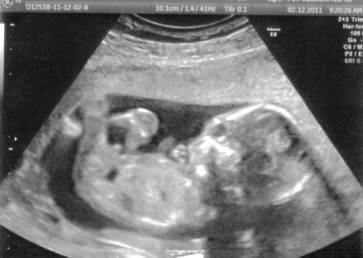

takže dovolte, abych vám představila našeho prďoška :-) na té druhé fotce ovšem vypadá jak UFOnek :-)

oprava, ufonek je na té trojfotce, hned ta první, ta poslední je pak zvětšená a to je ta druhá fotka a kdo najde pindíka????

No, to je už nádherné, obrovské miminko, Yashi! To je úžasné a dojemné! Pindíka vidím

[59518]Yashi máš krásné miminko pod srdíčkem, podle UZ se mu ve Tvém bříšku strašně moc líbí

podle toho jak si tam hoví

[59518] yashi, to je krásné. Jde nádherně vidět, že to je chlapeček. :-) To já mám s posledního UZ spíš fotku medvídka, kulatá hlavička, kulaté bříško a jako by měl jen takové kulaté pacinky, které mu trčí z bříška. :-)